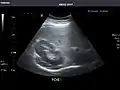

Abdominal ultrasound can be used to diagnose abnormalities in various internal organs, such as the kidneys,[1] liver, gallbladder, pancreas, spleen and abdominal aorta. If Doppler ultrasonography is added, the blood flow inside blood vessels can be evaluated as well (for example, to look for renal artery stenosis). It is commonly used to examine the uterus and fetus during pregnancy; this is called obstetric ultrasonography.[2][3]

Through the abdominal wall, organs inside the pelvis can be seen, such as the urinary bladder or the ovaries and uterus in women. Because water is an excellent conductor for ultrasound waves, visualizing these structures often requires a well-filled urinary bladder (this means the patients has to drink plenty of water before the examination).